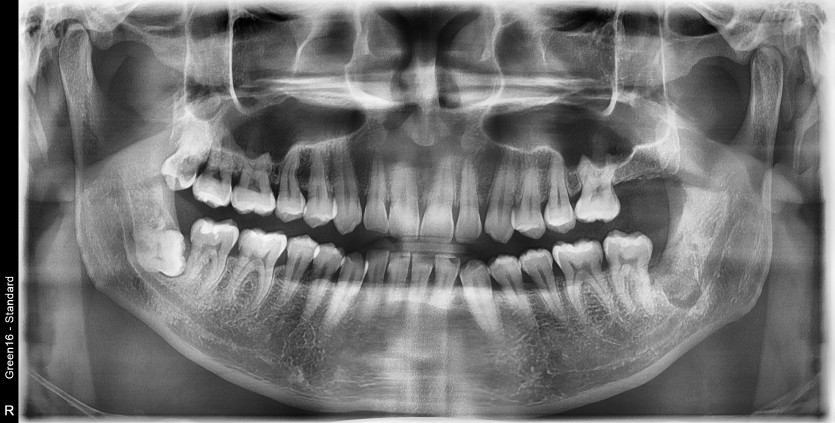

#38 사랑니 발치

구강 외과 전문의가 당일 발치했습니다.